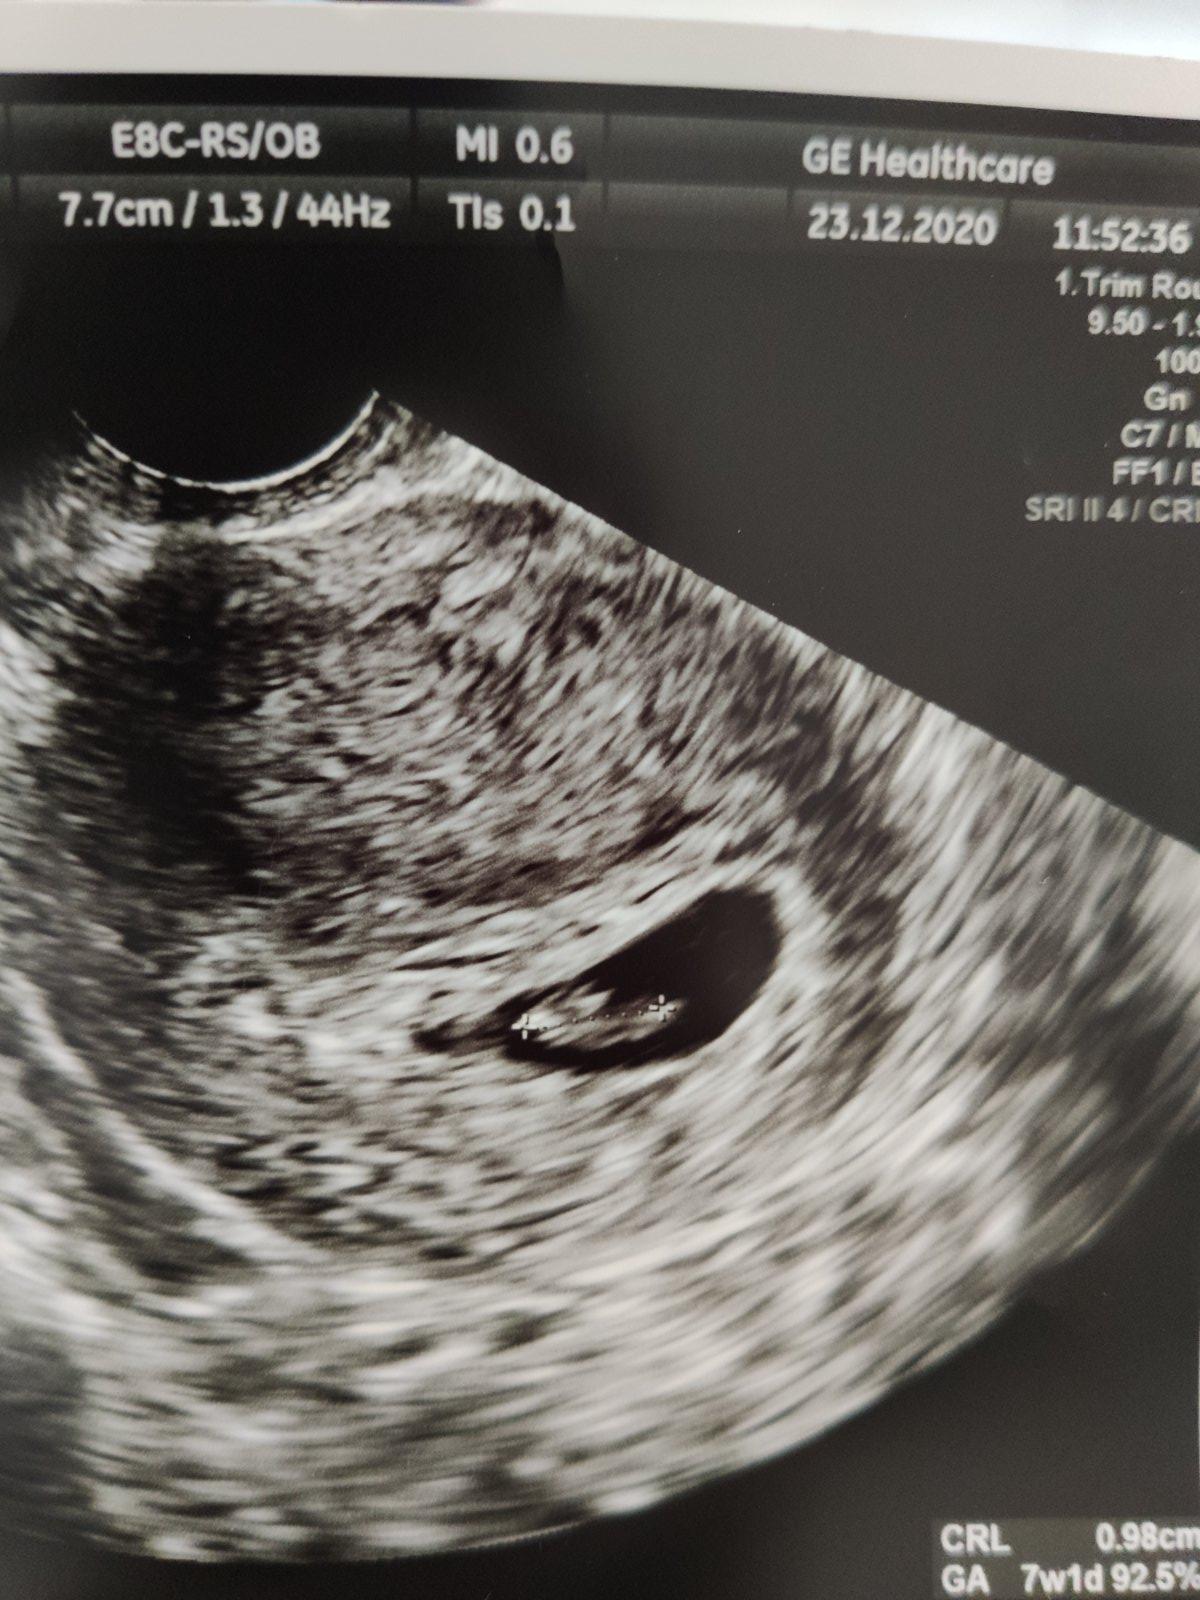

Takže baby podľa PM som 6+4a bolo vidieť aj srdiečko. Plod je menší o 4 dní cize 6+0. O dva týždne kontrola. Veľmi sa teším. Má 3.5 mm.

@miskachrumka ahoj ano ja mam prvú fotku 😊 podla ms 7+0 a podla velkosti 7+1 😊srdiecko krasne bilo 😊 momentalne som 8+3 a dalsiu kontrolu mam 12.1.

@dadus_ka aj ja mám .... Naše malo 1cm

Áno, plodik už je. Taka mala bodka 🙂